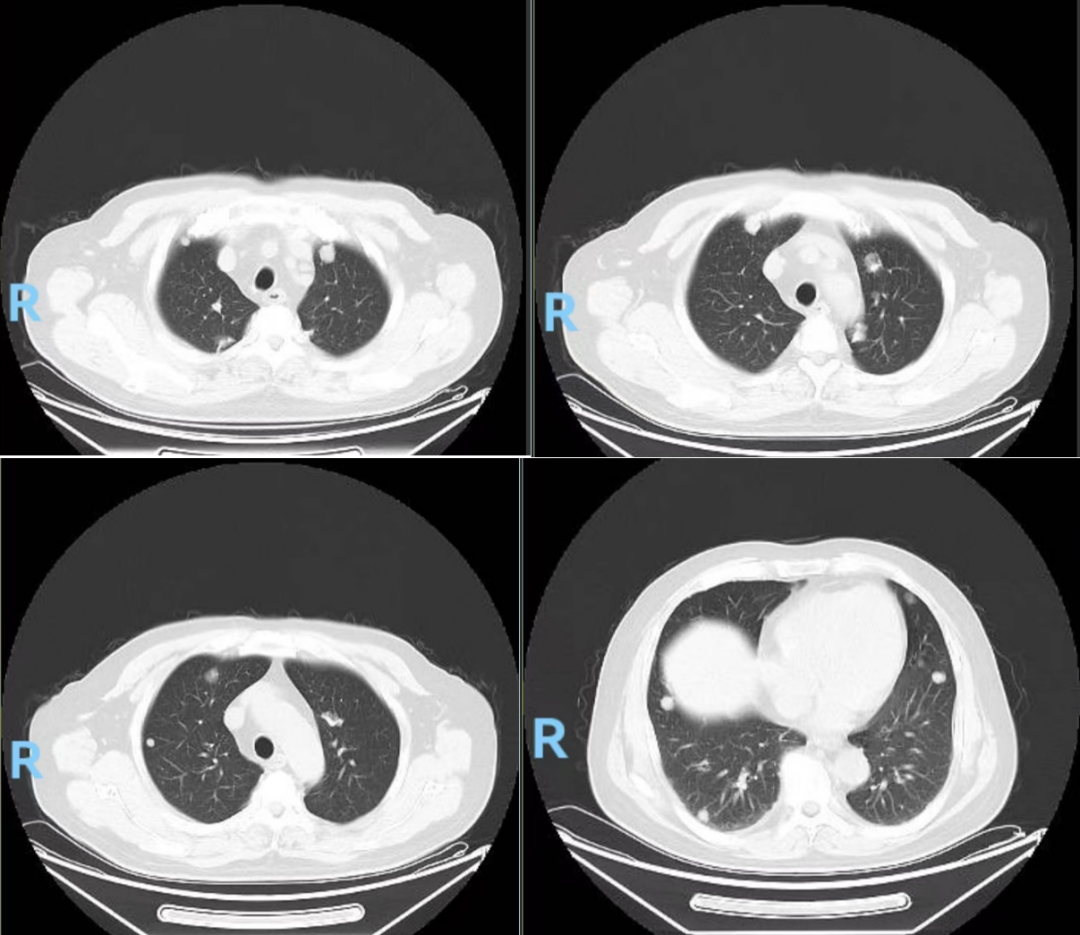

胸部CT(图2,2024-04-18):1.双肺多发结节灶、纵隔、腹膜后多发淋巴结肿大,考虑:肺内多发转移,纵隔淋巴结转移、腹膜后淋巴结转移可能;2.T9椎体骨质破坏,转移可能大。

图2.胸部CT(2024-04-18):双肺可见多发结节状密度灶,较大者直径约2cm,右肺中叶外侧段支气管受压,欠通畅。纵隔3、4R、6、7、10R区可见多发肿大淋巴结。T9椎体可见骨质破坏,密度欠均。诊断:1.双肺多发结节灶、纵隔、腹膜后多发淋巴结肿大,考虑:肺内多发转移,纵隔淋巴结转移、腹膜后淋巴结转移可能;2.T9椎体骨质破坏,转移可能大

图6.复查胸部CT(2024-09-19):胸廓对称,肋骨走行连续;双肺可见散在小斑片状、小条片状及结节状密度增高影,边界清。双肺可见少量纤维条索影,边界清。双肺可见多发结节灶,较大位于左肺上叶前段(IM12),大小约12mmx6mm。诊断:1.双肺多发结节灶;双肺索条、慢性炎症,较有所好转;2.胸9椎体变扁并密度不均,转移瘤并病理性骨折